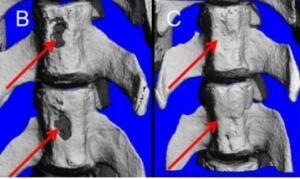

Les chercheurs testent ici une combinaison de cellules souches mésenchymateuses (dérivées de la moelle osseuse), provenant d’adultes et l’hormone parathyroïde (PTH) sur l’animal. Chez l’Homme, l’hormone PTH régule le taux de calcium et assure donc une fonction essentielle dans la santé et la solidité des os. Durant 21 jours, les animaux de laboratoire (rats et porcs), présentant des fractures vertébrales ont reçu des injections quotidiennes de PTH et, durant cette même période, 5 injections de cellules souches. L’effet thérapeutique de la combinaison cellules souches-PTH a été comparé aux résultats de la  thérapie par cellules souches seule, des injections de PTH seule, et à l’absence de traitement. La régénération osseuse a été contrôlée à plusieurs reprises par scanner.

thérapie par cellules souches seule, des injections de PTH seule, et à l’absence de traitement. La régénération osseuse a été contrôlée à plusieurs reprises par scanner.

L’étude montre qu’à la fois les cellules souches et l’hormone ont un effet bénéfique sur le processus de guérison des fractures : la migration des cellules souches vers la zone de fracture de l’os est accélérée et la formation osseuse augmentée. Mais l’étude montre que la combinaison cellules souches et PTH démultiplie ces effets, permet d’augmenter de façon encore plus significative la formation d’os –multipliée par 3 ou 4, vs chaque thérapie solo- et finalement accélère le processus de cicatrisation de ces fractures osseuses causées par l’ostéoporose.